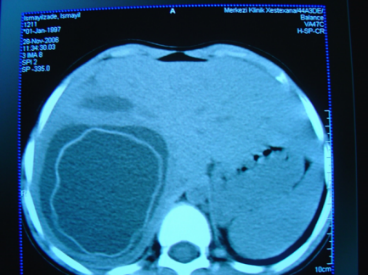

QARACİYƏRİN DAMAR XƏSTƏLİKLƏRİ

N.Y.Bayramov, R.A.Məmmədov

BADDİ-KİARİ SİNDROMU

Tərifi

Qaraciyərin venoz qan axınını ləngidən xəstəliklər tıxanma səviyyəsinə görə üç qrupa ayrılır.

Birinci qrup, sinus və kiçik venaların trombozu və sklerozu ilə xarakterizə olunan venookluziv xəstəliklər adlanır

Böyük qaraciyər venalarının tıxanması nəticəsində meydana gələn venoz durğunluq Baddi-Kiari sindromu adlanır. Baddi-Kiari sindromunda qaraciyər venaları ilə yanaşı aşağı boş venada da tıxanma ola bilir.

Ekstrahepatik venostaz adlanan üçüncü qrupda isə, qaraciyərüstü aşağı boş venada qan axını əngəllənir. Sağ ürək yetməzliyi, konstruktiv perikardit, aşağı boş vena daralmaları (tromboz, membran, fibroz, şiş və s.) bu qrupa aiddir. Baddi-Kiari sindromundan fərqli olaraq, ekstrahepatik venostazda qaraciyər venaları nəinki açıq olur, hətta genişlənir.

Diaqnostikası

Dəqiqləşdirmə

• Diaqnozu dəqiqləşdirmək üçün Qc venaları yoxlanılmalıdır. Bunun üçün dopler USM, KT-angioqrafiya, MRT-angioqrafiyalar və ya kontrastlı venoqrafiya edilir.

• Görüntüləmədə Qc venalarının trombotik tutulması diaqnozu dəqiqləşdirən əlamətdir.